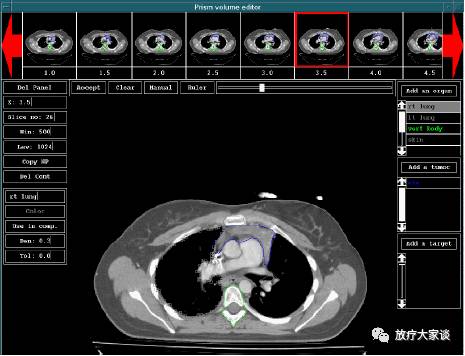

4.2 轮廓编辑

放疗计划系统有哪些放射治疗计划系统(TPS)介绍_https://www.jmylbn.com_新闻资讯_第4张